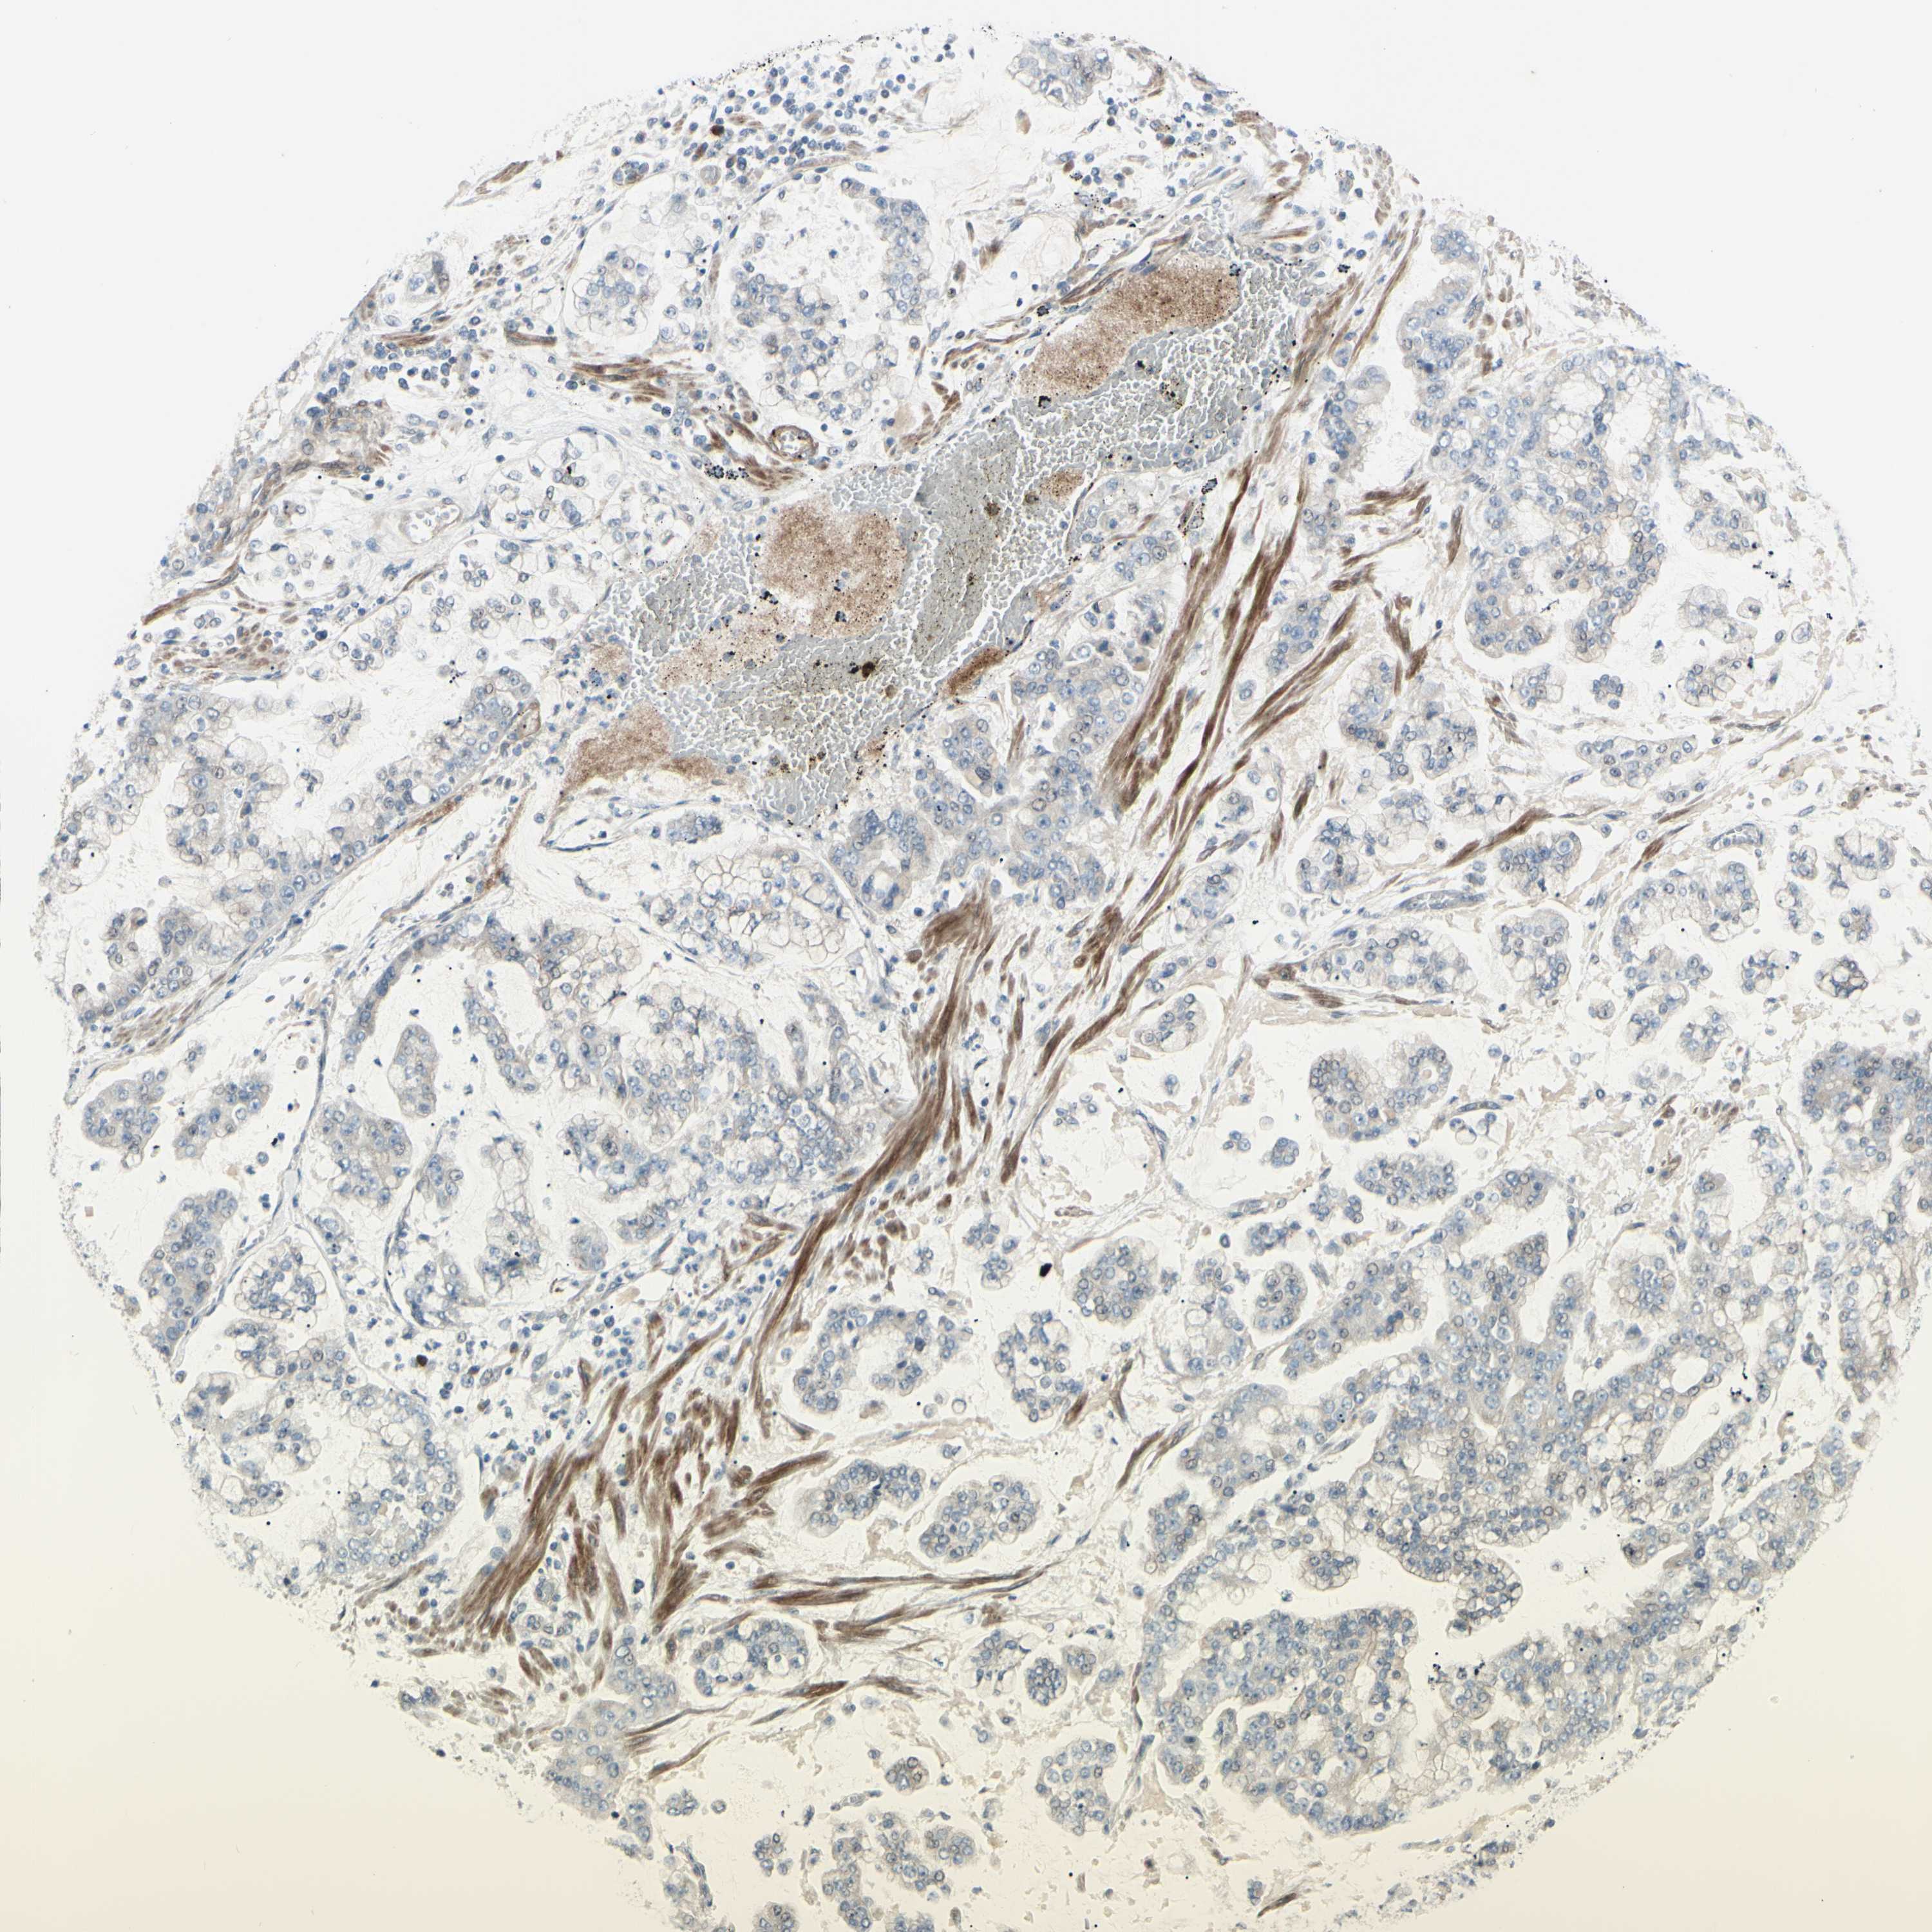

STOMACH CANCER - Protein expressioni

A mouse-over function shows sample information and annotation data. Click on an image to view it in a full screen mode. Samples can be filtered based on level of antibody staining by selecting one or several of the following categories: high, medium, low and not detected. The assay and annotation is described here.

Note that samples used for immunohistochemistry by the Human Protein Atlas do not correspond to samples in the TCGA dataset.

Antibody stainingi

Antibody staining in the annotated cell types in the current human tissue is reported as not detected, low, medium, or high, based on conventional immunohistochemistry profiling in selected tissues. This score is based on the combination of the staining intensity and fraction of stained cells.

Each image is clickable and will lead to virtual microscopy that enables deeper exploration of all samples and also displays staining intensity scores, fraction scores and subcellular localization as well as patient and tissue information for each sample.

Antibody HPA010537

Staining

High

Medium

Low

Not detected

Intensity

Strong

Moderate

Weak

Negative

Quantity

>75%

75%-25%

<25%

None

Location

Nuclear

Cytoplasmic/membranous

Cytoplasmic/membranous,nuclear

Adenocarcinoma, NOS

Adenocarcinoma, High grade